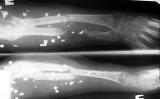

Огнестрельный дефект предплечья

На рентгенограммах приведены картинки - одна без вмешательств, другая в условиях ручной тракции по оси предплечья. Кисть была полностью нефункциональна - сгибательные контрактуры всех пальцев, выраженный отек кисти, Было решено, что тактику лечения определим после попытки восстановления функции кисти. На сегодня - полное восстановоение объема движений в пальцах за исключением активного отведения 1 пальца. Больная даже вяжет на спицах. Больная не очень дисциплинирована, выписывалась из стационара за алкогольные радости, длительное лечение с использованием ЧКДОС мало реально.